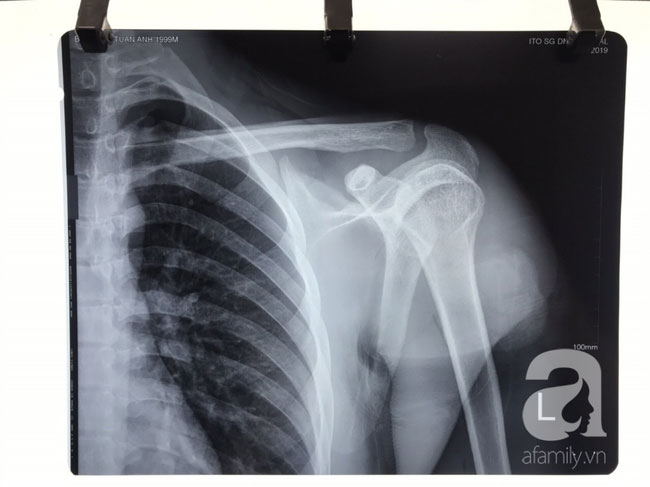

Trường hợp trên của bệnh nhân T.A (20 tuổi, trú tại Biên Hòa). Nam thanh niên nhập viện trong tình trạng vai trái bị vết thương xuyên thấu, chảy nhiều máu, cánh tay trái tê buốt, khuỷu tay và cổ tay trái không cử động được.

Bệnh nhân cho biết, trong khi đi chơi với bạn bè có xảy ra xô xát với nhóm người lạ và bị phóng dao xuyên qua vai.

Bác sĩ Phạm Đình Vinh, Khoa Chấn thương chỉnh hình, bệnh viện Hoàn Mỹ ITO Đồng Nai thông tin, qua thám sát vết thương, phát hiện dây thần kinh quay và thần kinh cơ bì cánh tay trái của bệnh nhân bị đứt hoàn toàn.

Nghi ngờ vết thương đã làm tổn thương đến thần kinh, kíp trực tiến hành các xét nghiệm thăm dò. Kết quả điện cơ cho thấy, bệnh nhân bị tổn thương sợi trục dây thần kinh quay và thần kinh bì cánh tay.